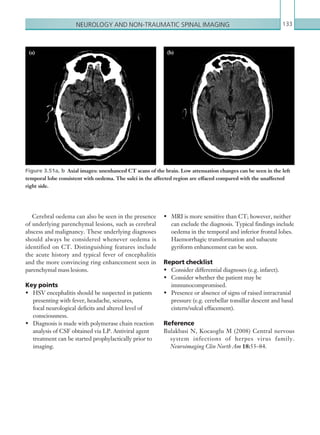

• 14.

Contentsx HERPES SIMPLEX ENCEPHALITIS131 Radiological investigations 132 Radiological findings 132 Magnetic resonance imaging 132 Computed tomography 132 Key points 133 Report checklist 133 Reference133 SPINAL CORD COMPRESSION AND CAUDA EQUINE SYNDROME 134 Radiological investigations 134 Radiological findings 134 Magnetic resonance imaging 134 Key points 136 Report checklist 136 SPONDYLODISCITIS137 Radiological investigations 137 Radiological findings 138 Magnetic resonance imaging 138 Plain films 139 Key points 140 Report checklist 140 References140 CHAPTER 4: PAEDIATRIC IMAGING 141 INTUSSUSCEPTION141 Radiological investigations 141 Radiological findings 141 Ultrasound141 Fluoroscopic air enema 142 Plain films 143 Computed tomography 143 Key points 143 Report checklist 143 Reference143 BOWEL MALROTATION 143 Radiological investigations 143 Radiological findings 144 Upper gastrointestinal contrast study 144 Ultrasound144 Computed tomography 145 Plain films 145 K22247_FM.indd 10 16/05/15 3:05 AM

• 15.

Contents xi Key points145 Report checklist 145 MECONIUM ILEUS 145 Radiological investigations 145 Radiological findings 146 Lower gastrointestinal contrast study 146 Plain films 146 Key points 147 Report checklist 147 DUODENAL ATRESIA 147 Radiological investigations 147 Radiological findings 148 Plain films 148 Upper gastrointestinal contrast study 149 Key points 149 Report checklist 149 HYPERTROPHIC PYLORIC STENOSIS 149 Radiological investigations 149 Radiological findings 150 Ultrasound150 Key points 151 Report checklist 151 ORBITAL AND PERIORBITAL CELLULITIS 151 Radiological investigations 151 Radiological findings 152 Computed tomography 152 Key points 153 Report checklist 153 ACUTE OTITIS MEDIA 154 Radiological investigations 154 Radiological findings 154 Computed tomography 154 Key points 155 Report checklist 155 Reference155 PARAPHARYNGEAL AND RETROPHARYNGEAL ABSCESS 156 Radiological investigations 156 Radiological findings 157 Computed tomography 157 Key points 159 Report checklist 159 Reference159 K22247_FM.indd 11 16/05/15 3:05 AM

• 16.

Contentsxii CHAPTER 5: TRAUMAIMAGING 161 INTRODUCTION TO IMAGING IN MAJOR TRAUMA 161 Penetrating injury 163 Active haemorrhage 163 Blunt injury 166 Key points 166 Reference166 MAJOR TRAUMA: THORAX 167 Radiological investigations 167 Radiological findings 168 Mediastinal injury 168 Cardiac injury 168 Pneumothorax169 Haemothorax170 Rib fracture and flail chest 171 Lung contusion and lung laceration 172 Diaphragmatic injury 172 Key points 172 Report checklist 172 References172 MAJOR TRAUMA: ABDOMEN AND PELVIS 173 Radiological investigations 173 Radiological findings 174 Solid organ injury 176 Mesenteric and bowel injury 178 Pelvic injury 180 Bladder and urethral injury 180 Key points 182 Report checklist 182 References182 MAJOR TRAUMA: SPINE 182 Radiological investigations 183 Radiological findings 184 Plain films 184 Computed tomography 184 Magnetic resonance imaging 185 Examples of spinal fractures 185 Jefferson fracture 185 Odontoid peg fractures 186 Flexion teardrop fracture 186 K22247_FM.indd 12 16/05/15 3:05 AM